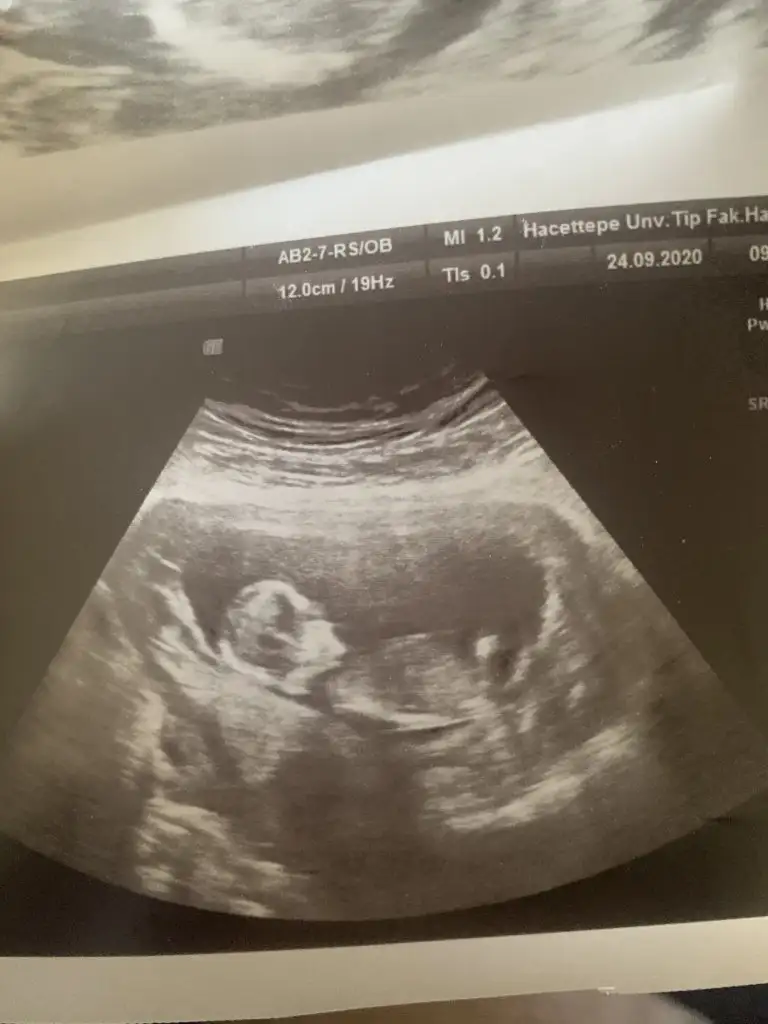

Nubu yüksek görünüyor sanki net değil karışık görünüyor emin olamadimBaşka usg yok doktor kıza benziyor demisti ama net değil demisti

Canım 11 de büyük olasılık kız 12 de nubu kalktı kız da olabilir erkek de dedi. 15 te %100 kız dedi 16 da hala kız dediSize 12.haftada doktor, erkek mi dedi?

Kız gibi sanki kaç haftalık usgler 11 12 13 haftalar olmalı

12 haftalıkKız gibi sanki kaç haftalık usgler 11 12 13 haftalar olmalı

Sağlıkla gelsin prenses anket için çok teşekkür ederimIkra meyra En son size sormuştum kız sanki demiştiniz doğru cıktı bugün öğrendim kızımız oluyor inşallah cok teşekkür ediyorum :)))

Merhaba tahmininiz doğru çıktı doktorumuz %95 kız dediDr tam -----+ nubtan geçmiş ölçümü emin değilim sanki kız 11 12 13 haftalar olursa paylasin

Sağlıkla gelsin prensesMerhaba tahmininiz doğru çıktı doktorumuz %95 kız dedi![]()